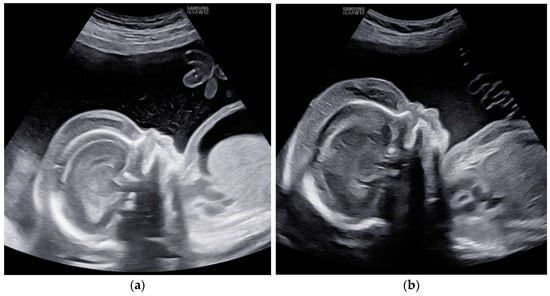

Also, a total resolution of fetal hydrops was observed (Figure 6).

Figure 6. Case 6: Total resolution of ascites (a) before first intrauterine transfusion, 24 weeks of gestational age; (b) 2 weeks after second intrauterine transfusion, 28 weeks of gestation.

Children 11 01037 g006